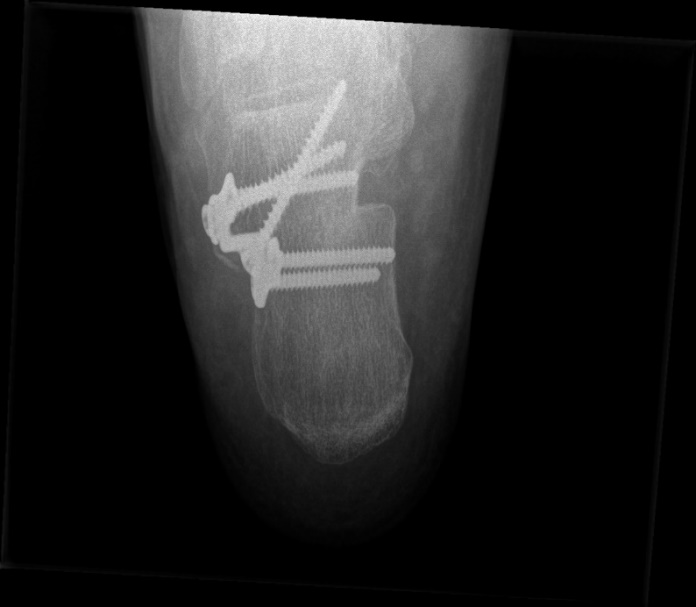

Van zodra de voet volgroeid is, kan er geen gebruik meer gemaakt worden van een implantaat. Er zal een beenderige correctie nodig zijn in combinatie met het ligamentair herstel. Bij deze ingreep wordt het calcaneum (hielbeen) doorgezaagd en op deze wijze verplaatst zodat het verschoven calcaneum (verworven door de platvoet) terug onder de patiënt kan worden geschoven, waardoor het weer een optimale steun gaat geven en de vorm van de voet wordt veranderd.

Voor de fixatie van het bot wordt er een speciaal plaatje met trapvorm aangebracht op het verschoven calcaneum (zie radiografie verder). Dit plaatje wordt gefixeerd met 5 stevige schroeven.